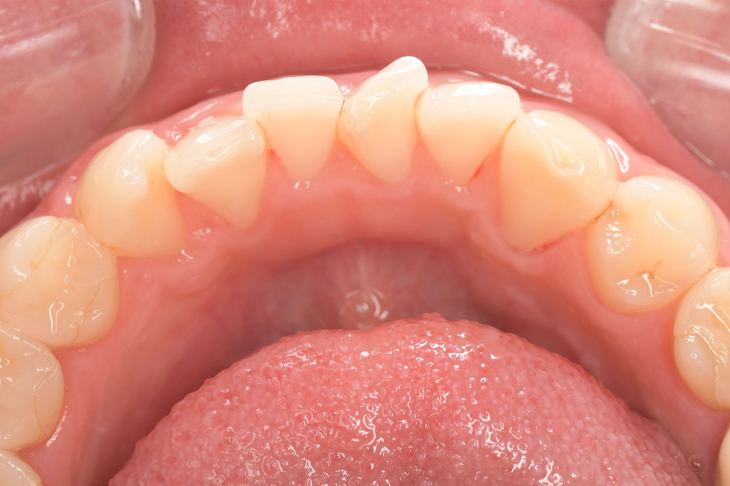

Before

After

基本情報

| 主訴 | 見た目をきれいにしたい |

| 治療期間 | 6ヶ月 |

| 治療費 | ジルコニアボンド(セラミックの被せもの)¥165,000×7(税込み) オフィスホワイトニング4回 ¥4,400×4(税込み) ホームホワイトニング¥11,000 |

| リスク・副作用 | かみ合わせがとても強い方の場合、稀に割れてしまうことがあります。 |

| 先生からの提案 | 上の前歯6本と右下の2番目の歯はセラミックの被せもので治療。 残りの下の前歯5本はプラスチックの材料で虫歯を治療し、 ホワイトニングをおこないました。白くなったご自身の歯の色に合わせてセラミックの 被せものを作成しています。 模型上で完成後をシュミレーションし、上の歯茎の位置をきれいに見えるように 揃えています。(外科処置はしていません) |